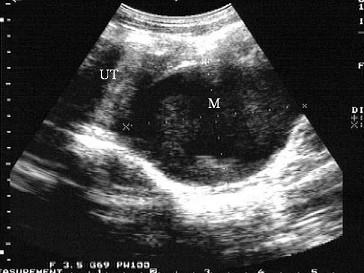

问题 女性,16岁,周期性下腹疼痛伴排尿困难。月经未来潮。超声检查见图,最可能的诊断是?(?)

选项 A.处女膜闭锁 B.子宫破裂 C.异位妊娠 D.宫颈囊肿 E.子宫肌瘤

答案 A